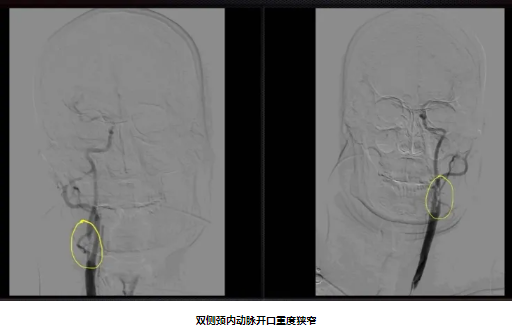

64岁男性,因“反复头晕3月”入院,既往有“脑梗死、高血压病、糖尿病”史。入院后完善颈动脉彩超及影像学检查提示:双侧颈内动脉开口重度狭窄。经颈动脉狭窄MDT团队充分讨论,结合斑块性质及患者临床需求,脑血管外科团队予患者行右侧颈动脉内膜剥脱术。术后第二天患者即能下床,术后3天复查CTA提示颈动脉狭窄得到明显改善。